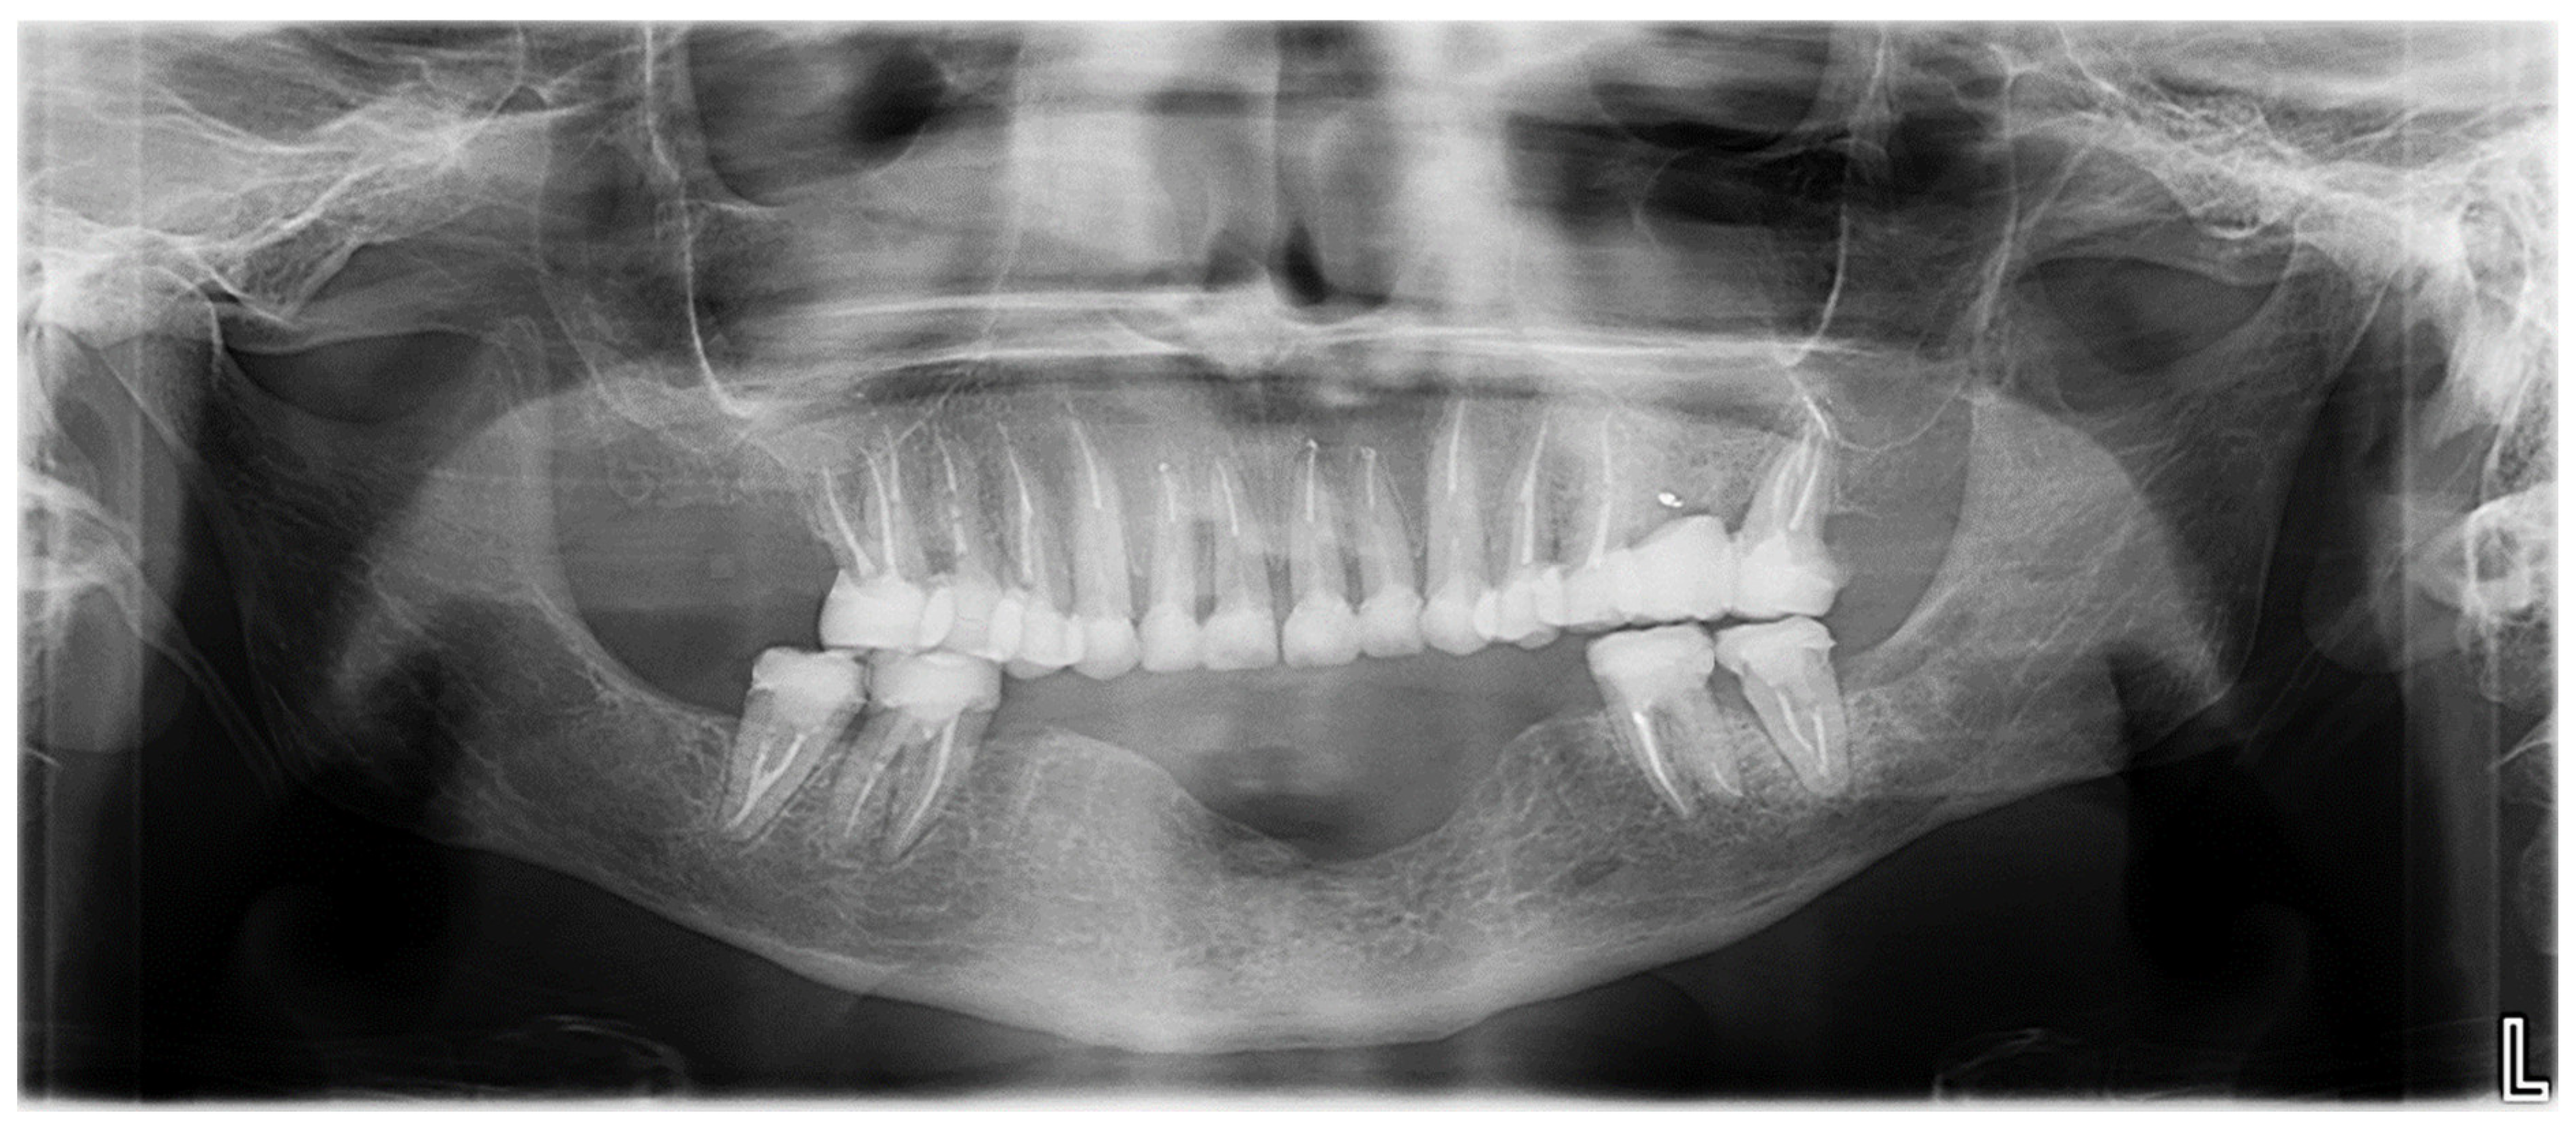

For the mandibular metal-framed removable partial denture, a digital impression was made using the 3Shape intraoral scanner. After the framework try-in, maxillomandibular relationship records were obtained using Aluwax (Aluwax Dental Products Co., Allendale, MI, USA), to accurately mount the casts on the articulator. The set-up was evaluated before polymerization. Upon prosthesis insertion, the occlusion was verified to ensure group function. Figure 1B, Figure 7 and Figure 8 illustrate the final treatment outcome.

Occluded arches views after treatment: (A) right view, (B) front view, (C) left view.

Figure 8.

Panoramic radiograph after treatment.